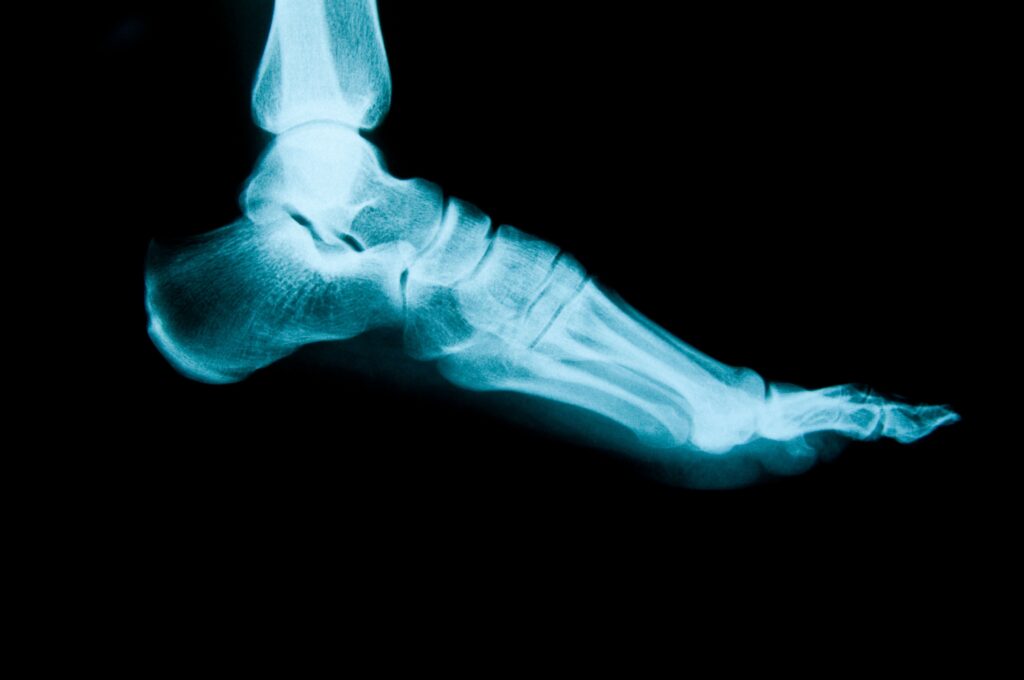

2. レントゲン検査

足の骨の変形の程度や、骨折・腫瘍の有無を確認します。